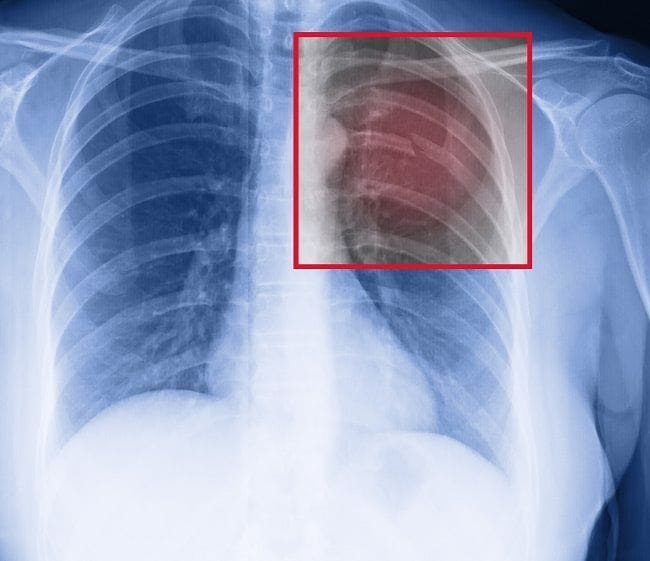

Dalam mendiagnosis patah tulang rusuk, dokter akan melakukan tanya jawab mengenai kejadian yang menyebabkan patah tulang rusuk. Selanjutnya, dokter akan melakukan pemeriksaan fisik pada area dada dan area tubuh lainnya untuk mencari kemungkinan cedera lain yang dialami pasien.

Pada saat pemeriksaan fisik, dokter juga akan mendengarkan suara napas pasien menggunakan stetoskop. Untuk menegakkan diagnosis, dokter dapat melakukan pemeriksaan penunjang berupa:

- Foto Rontgen dada

- CT scan dada